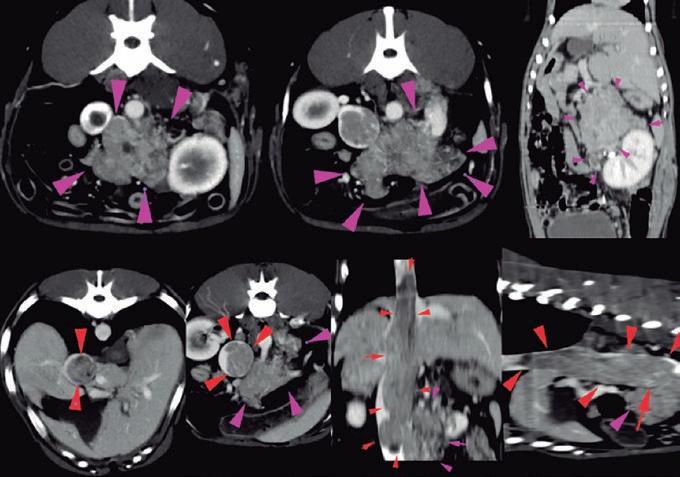

La responsabilidad de los artículos, reportajes, comunicados, etc. recae exclusivamente sobre sus autores. El editor sólo se responsabiliza de sus artículos o editoriales. La ciencia veterinaria está sometida a constantes cambios. Así pues es responsabilidad ineludible del veterinario clínico, basándose en su experiencia profesional, el correcto diagnóstico de los problemas y su tratamiento. Ni el editor, ni los autores asumen responsabilidad alguna por los daños y perjuicios, que pudieran generarse, cualquiera que sea su naturaleza, como consecuencia del uso de los datos e información contenidos en esta revista. De acuerdo con la normativa vigente en materia de protección de datos Grupo Asís Biomedia, SL., es responsable del tratamiento de sus datos personales con la finalidad de enviarle comunicaciones postales de nuestras revistas especializadas, así como otras comunicaciones comerciales o informativas relativas a nuestras actividades, publicaciones y servicios, o de terceros que puedan resultar de su interés en base a su consentimiento. Para ello, Grupo Asís podrá ceder sus datos a terceros proveedores de servicios de mensajería. Podrá revocar su consentimiento, así como ejercer sus derechos de acceso, rectificación, supresión, oposición, limitación y portabilidad enviando un correo electrónico a protecciondatos@grupoasis.com, o una comunicación escrita a Grupo Asís en Centro Empresarial El Trovador, planta 8, oficina I, Plaza Antonio Beltrán Martínez 1, 50002, Zaragoza (España), aportando fotocopia de su DNI o documento identificativo sustitutorio e identificándose como suscriptor de la revista. Asimismo, si considera que sus datos han sido tratados de forma inadecuada,